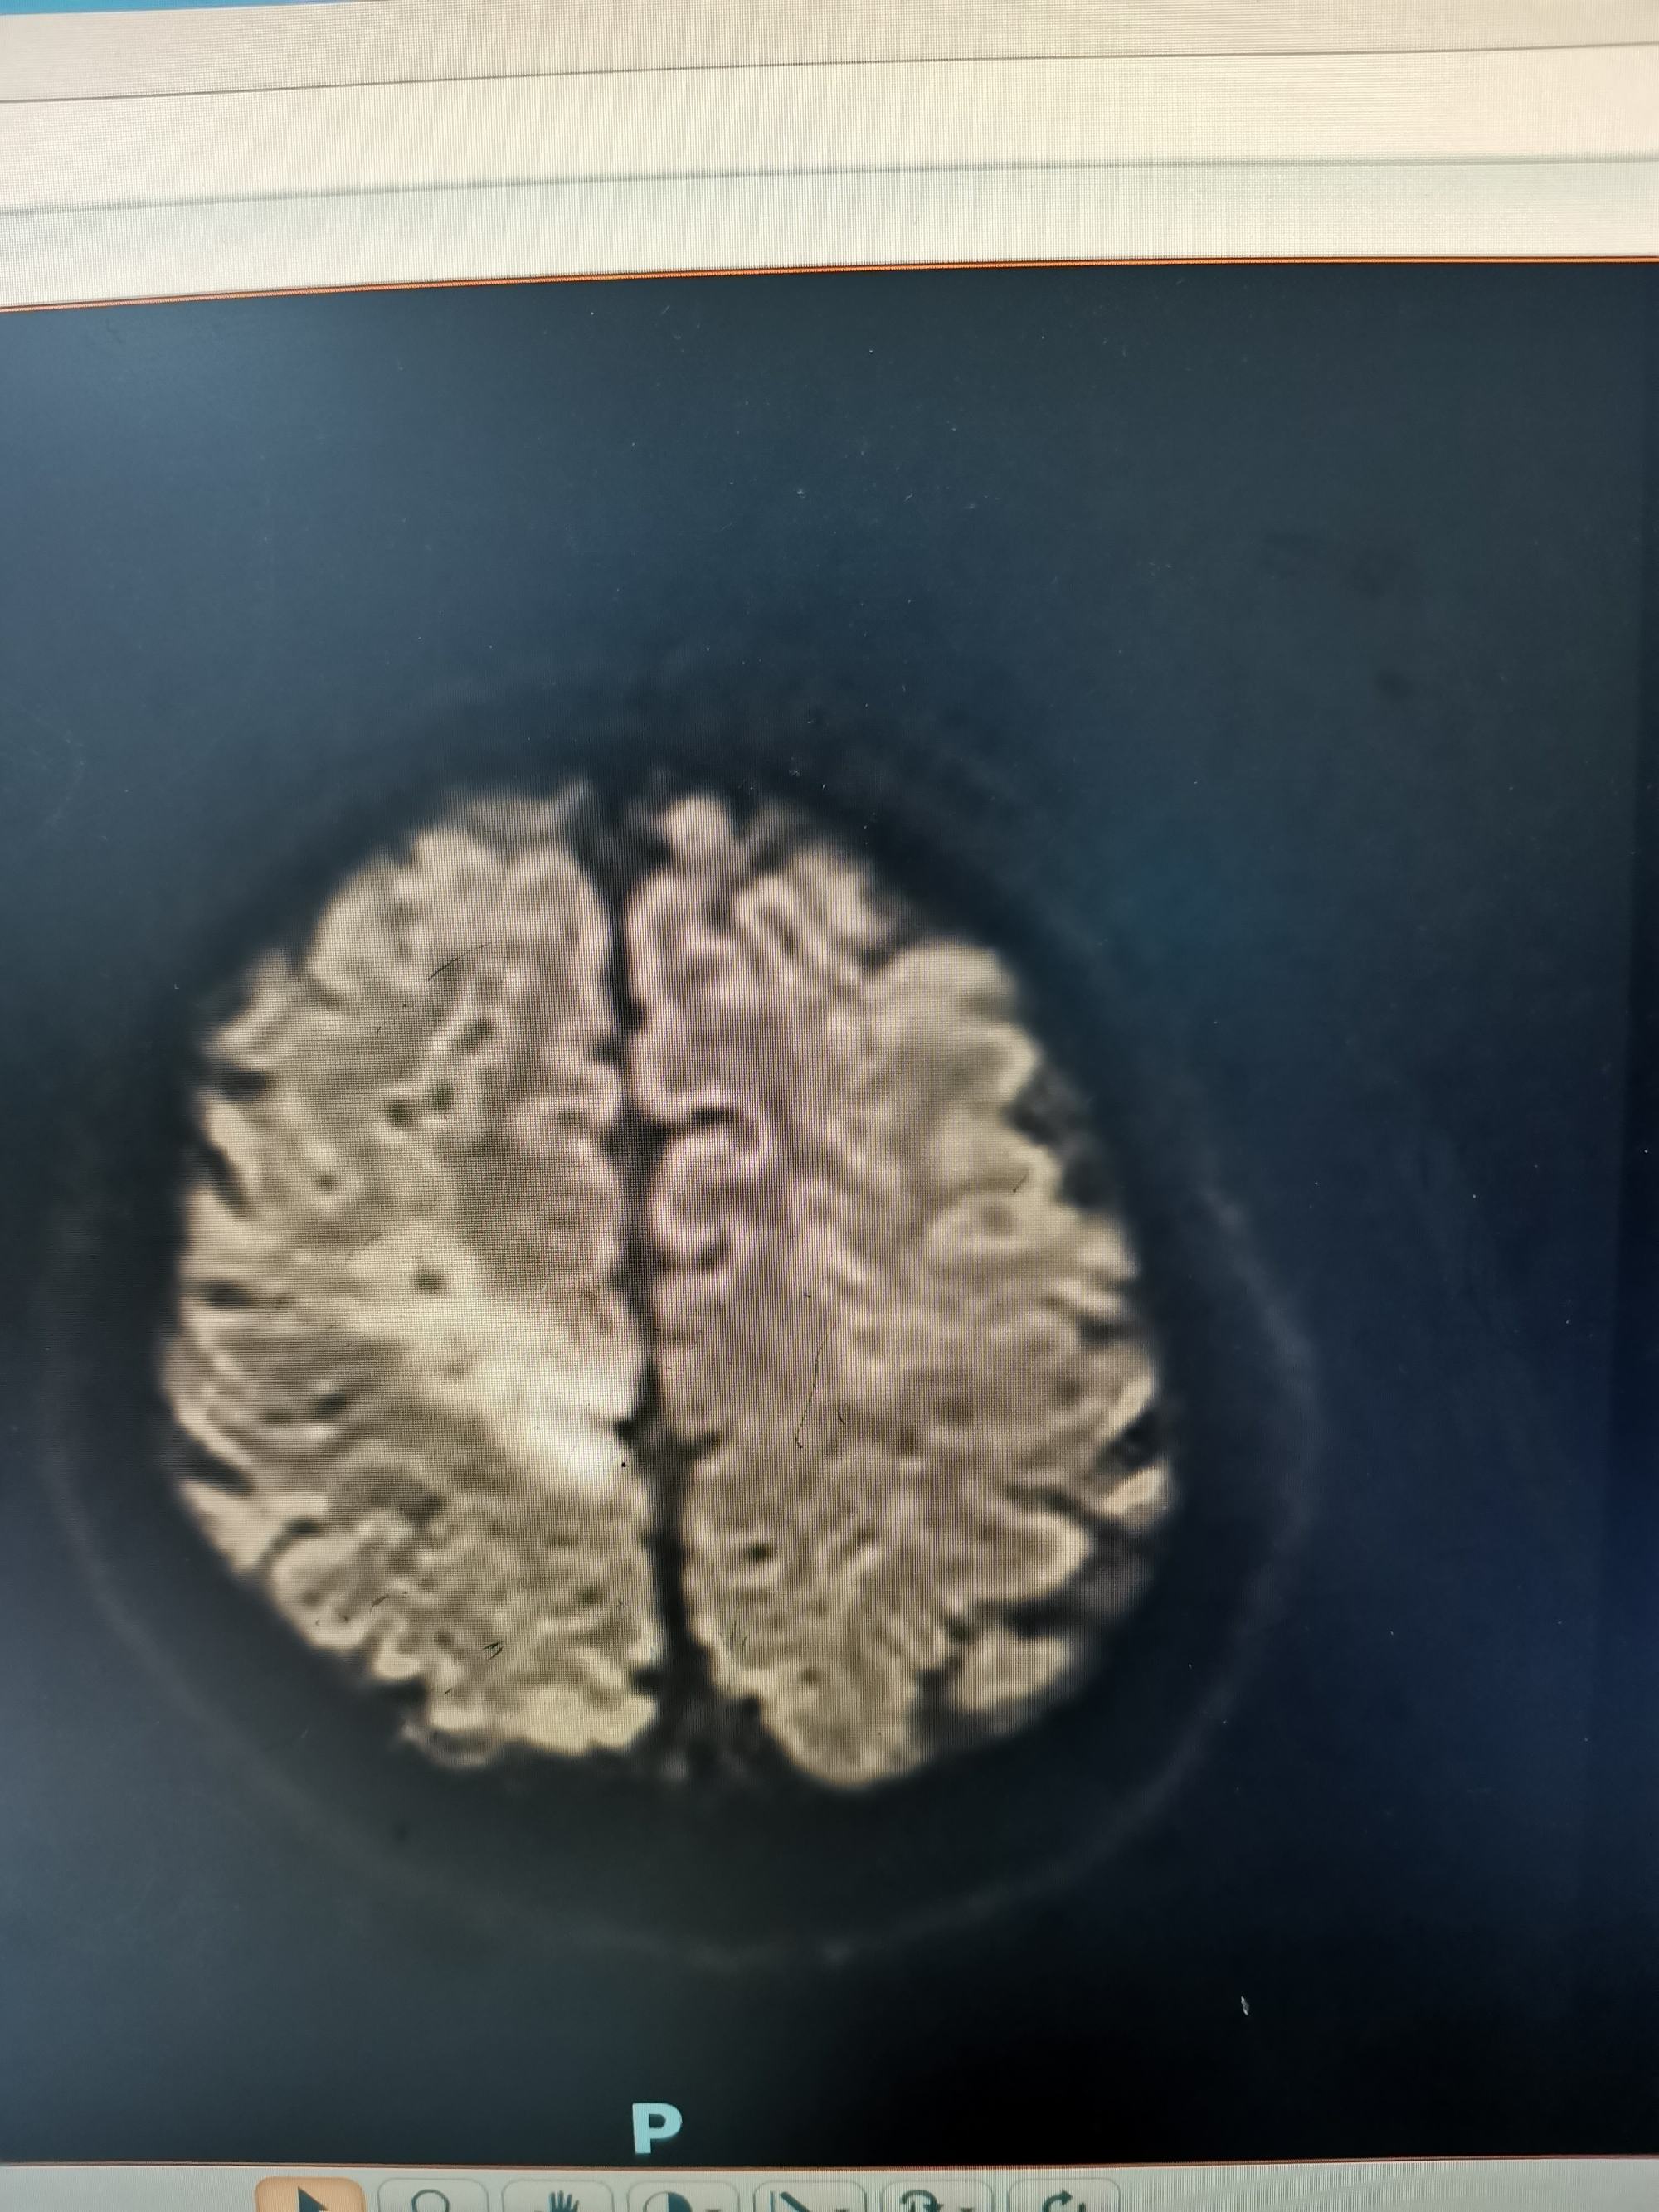

DWI考虑新发病灶为脑梗死,考虑该梗塞病灶位于运动皮层导致患者右下肢完全偏瘫。